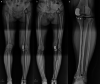

Unicompartmental knee arthroplasty (UKA) is a bone- and ligament-sparing alternative to total knee arthroplasty in the patients with end-stage single-compartment degeneration of the knee. Despite being a successful procedure, the multiple advantages of UKA do not correlate with its usage, most likely due to the concerns regarding prosthesis survivability, patient selection, ideal bearing design, and judicious use of advanced technology among many others. Therefore, the purpose of this study is to review and summarize the debated literature and discuss the controversies as "Ten Enigmas of UKA."